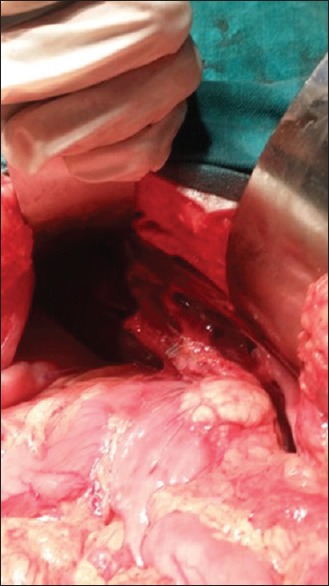

位置异常是一种罕见的结构缺陷,约占总人口的0.01%。他们表现出多系统的结构缺陷,主要涉及心血管、呼吸和胃肠道系统。存在多脾的位置异常被称为左心房异构体,其解剖和结构与脾不全的对应位置(右心房异构体)不同。在这个病例报告中,我们提出了一个成人病例的位置模糊异常是偶然诊断在腹腔镜胆囊切除术。患者肝左叶肿大,右侧多发脾,小肠和大肠旋转不良,下腔静脉中断伴奇静脉延续,双侧双叶肺。结论是,位置模糊情况的变化是不同的,单一的描述是不可能的。在手术和侵入性干预之前,利用成像方式揭示这些变异是至关重要的,以防止可能的风险和并发症。

Situs anomalies are rare structural defects affecting 0.01% of general population. They present with multisystem structural defects mostly involving cardiovascular, respiratory and GI systems. Situs abnormality with presence of multiple spleen is termed as left atrial isomerism with anatomical and structural differences to its countertype situs ambiguous with asplenia (right atrial isomerism). In this case report, we present an adult case of situs ambiguous anomaly which was diagnosed incidentally during laparoscopic cholecystectomy. The patient had enlarged left lobe of liver, multiple splenules on right side, malrotated small and large gut, interrupted inferior vena cava with azygos continuation, and bilateral bilobed lungs. It is concluded that variations in situs ambiguous cases differ and a single description is not possible. It is crucial to reveal these variations by using imaging modalities and being aware of them prior to surgery and invasive intervention to prevents the possible risks and complications.